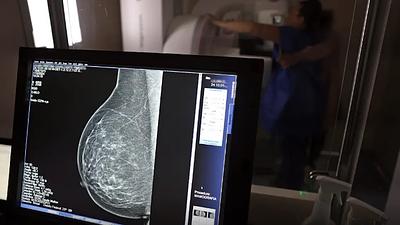

Os laudos dos exames de mamografia realizados no Centro Carioca de Diagnóstico e Tratamento por Imagem (CCDTI) são avaliados e assinados por profissionais médicos capacitados, no entanto, a IA auxilia na identificação de possíveis lesões difíceis de serem vistas.